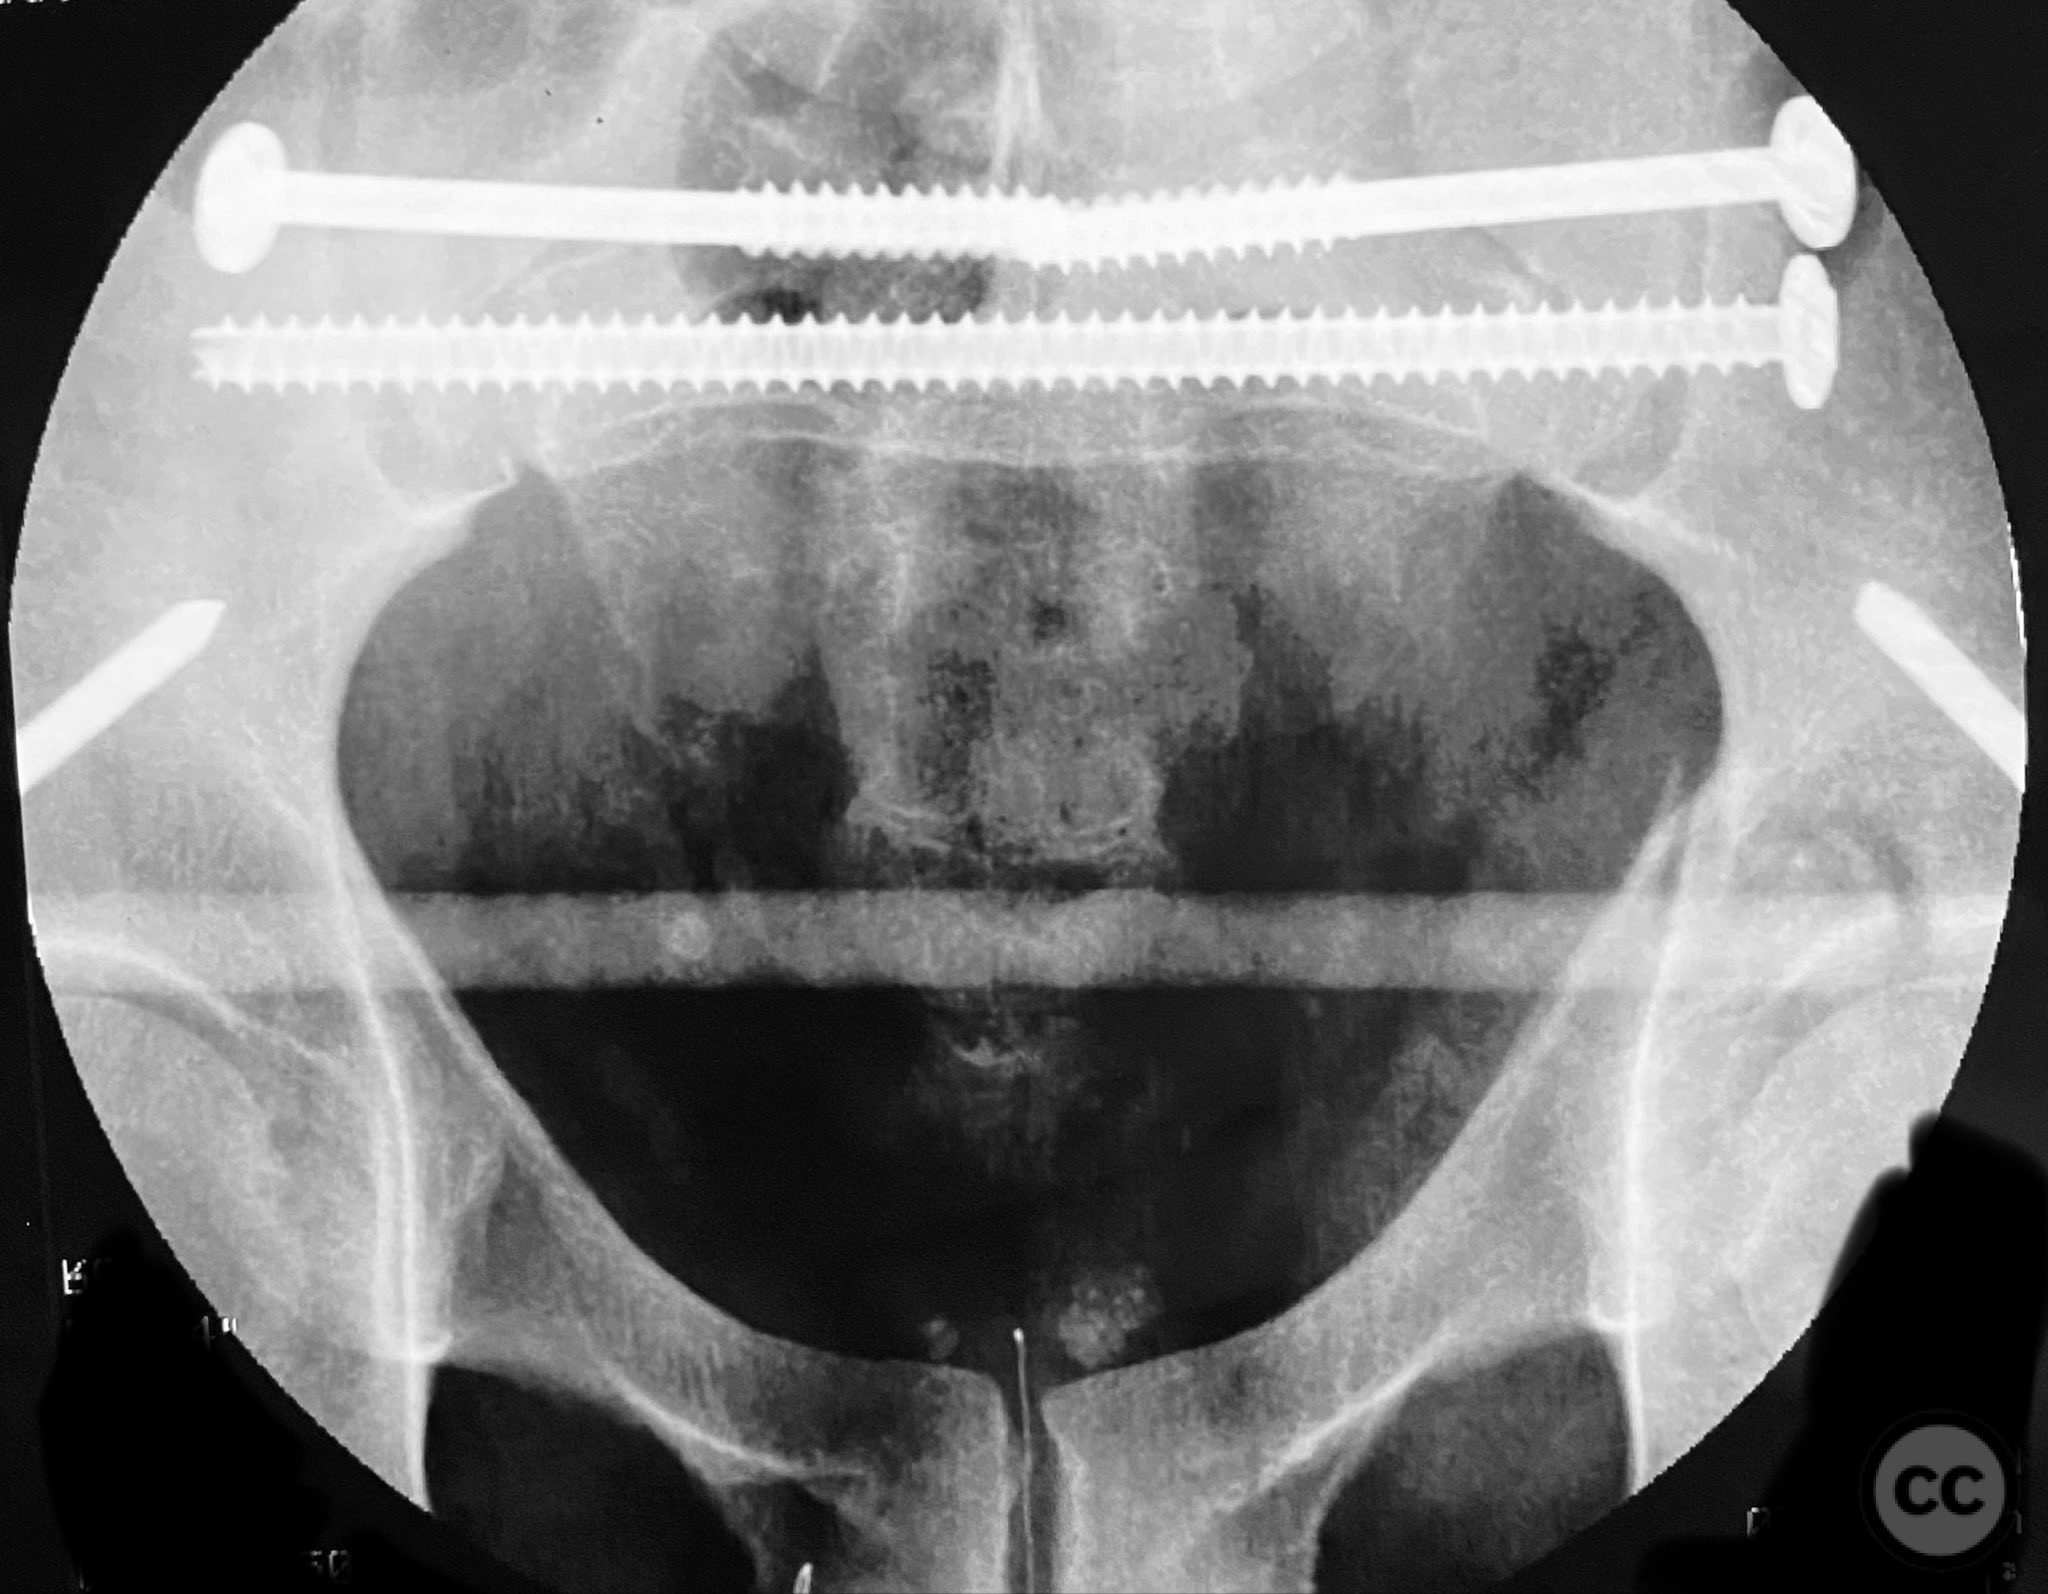

Planning remarks:  The preoperative plan involved staged management: initial resuscitation and provisional stabilization with a circumferential pelvic binder, followed by operative reduction and fixation of the pelvic ring using an anterior two-pin external fixator for SI joint compression and reduction, percutaneous iliosacral (IS) and transsacral (TS) screw fixation, and subsequent intramedullary nailing of the femur. Definitive acetabular fixation was planned via a posterior Kocher-Langenbeck approach in the prone position.

Orthopaedic implants used:   - Anterior two-pin external fixator - Percutaneous iliosacral screw(s) - Percutaneous transsacral screw(s) - Intramedullary femoral nail - 4.5 mm cortical screws (acetabular fixation) - Posterior column reconstruction plate(s)